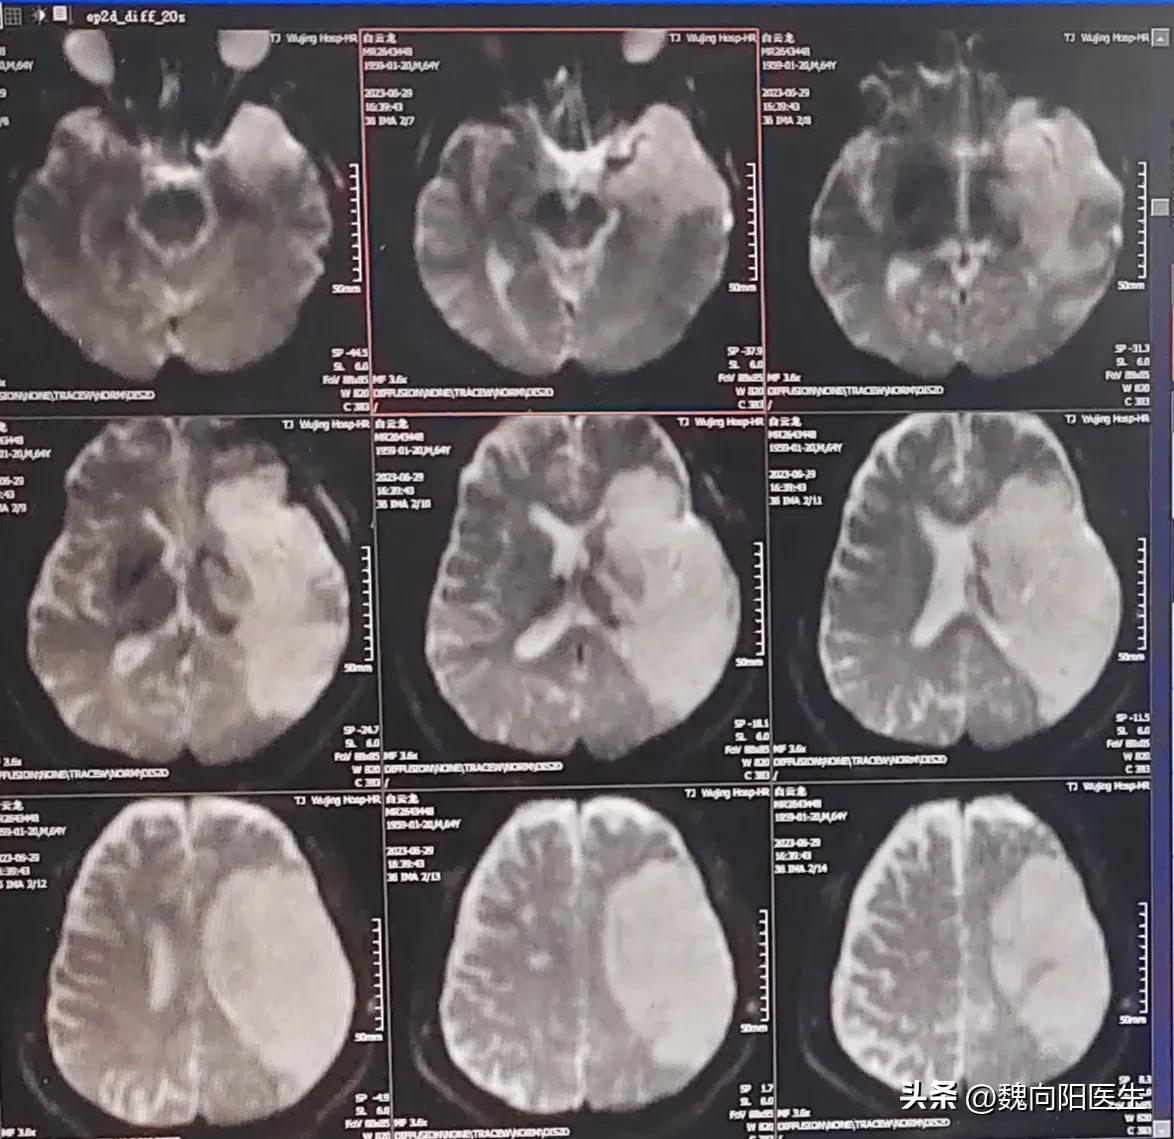

有一种脑梗死是叫做大面积脑梗死,由于大面积脑组织坏死之后,出现严重的脑水肿,引起明显的占位效应,压迫正常脑组织出现恶性循环。

具有占位效应的大面积脑梗死预后最差,占大脑半球脑梗死的2%~8%以及小脑梗死的4%~25%。

恶性脑水肿,大面积脑梗死发生之后会引起严重的水肿占位效应,有可能加重成脑肾,甚至死亡。